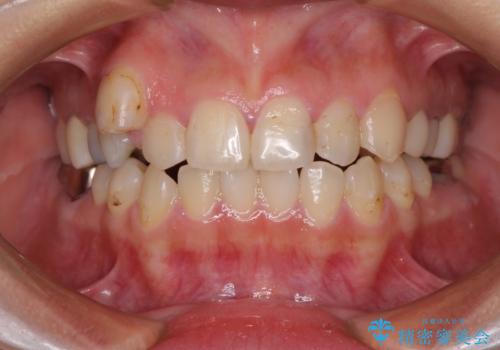

結婚式前にクリーニング希望の方

担当医 歯科衛生士